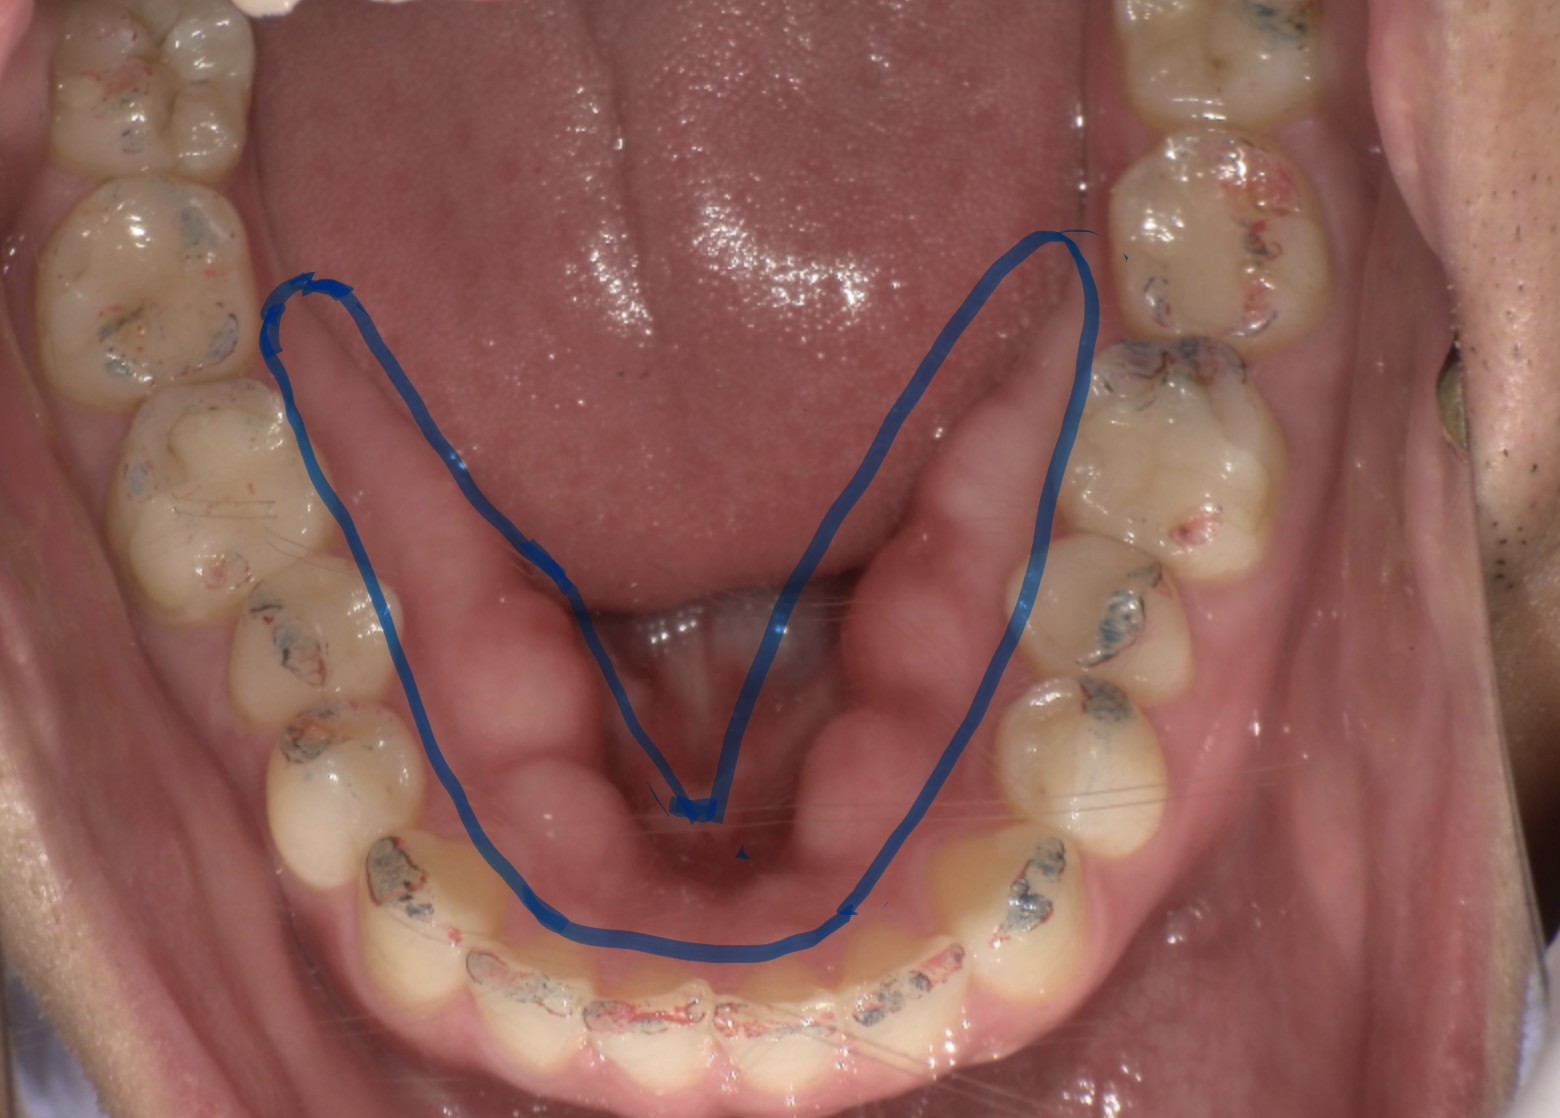

歯科臨床では、食いしばりなどが原因で長期間にわたり強い咬合圧が加わることで、顎の骨が盛り上がる「骨隆起(こつりゅうき)」が確認されることがあります。(下顎の内側に見られることが多いです。)

骨は持続的な力に適応する組織であり、骨隆起は“力の履歴”を示す所見の一つと考えられています。

青ラインで囲まれた範囲が骨隆起と言われる、食いしばりなどの力に反応して骨が盛り上がっている部分